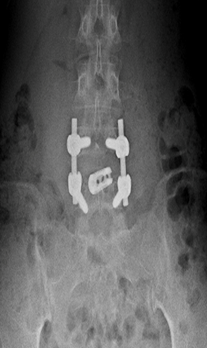

At presentation she had severe paraspinal spasm with movement restriction and no neurological deficits. Radiographs revealed a minimal reduction in L4/5 disc space . Hematological evaluation elevated showed TLC, ESR, CRP. MRI showed evidence of discitis at L4/5 with adjacent vertebral reactive changes( FIG 1,2). With a working diagnosis of post partum spondylodisctis she underwent a septic screening ( sputum, urine, blood cultures) and a CT guided biopsy which turned out to be negative. Considering her significant back pain  with limitations in suggesting antibiotics  she was suggested surgical debridement and fusion at L4/5. She underwent PLIF L4/5 under GA and had a drastic early pain relief . She was mobilized on post operative day – 1 with lumbo sacral brace. Her pain reduced significantly ( VAS 2/10) which needed minimal analgesics ( once a day paracetamol 1 gm intravenous infusion )for 5 days . She was able to turn in bed and sit to nurse the child. Her intraoperative tissues sent for culture grew pseudomonas which was sensitive to cefaperazone + sulbactum. She was initiated on intravenous antibiotics for 2 weeks duration and was followed up with further 4 weeks of oral antibiotics . Radiographs revealed fusion at L4/5 at 3 months( FIG 3,4) of follow up with serological markers normalizing by 6 weeks.

Fig 3: L4/5 PLIF- AP view

Fig 4: L4/5 PLIF- Lateral view